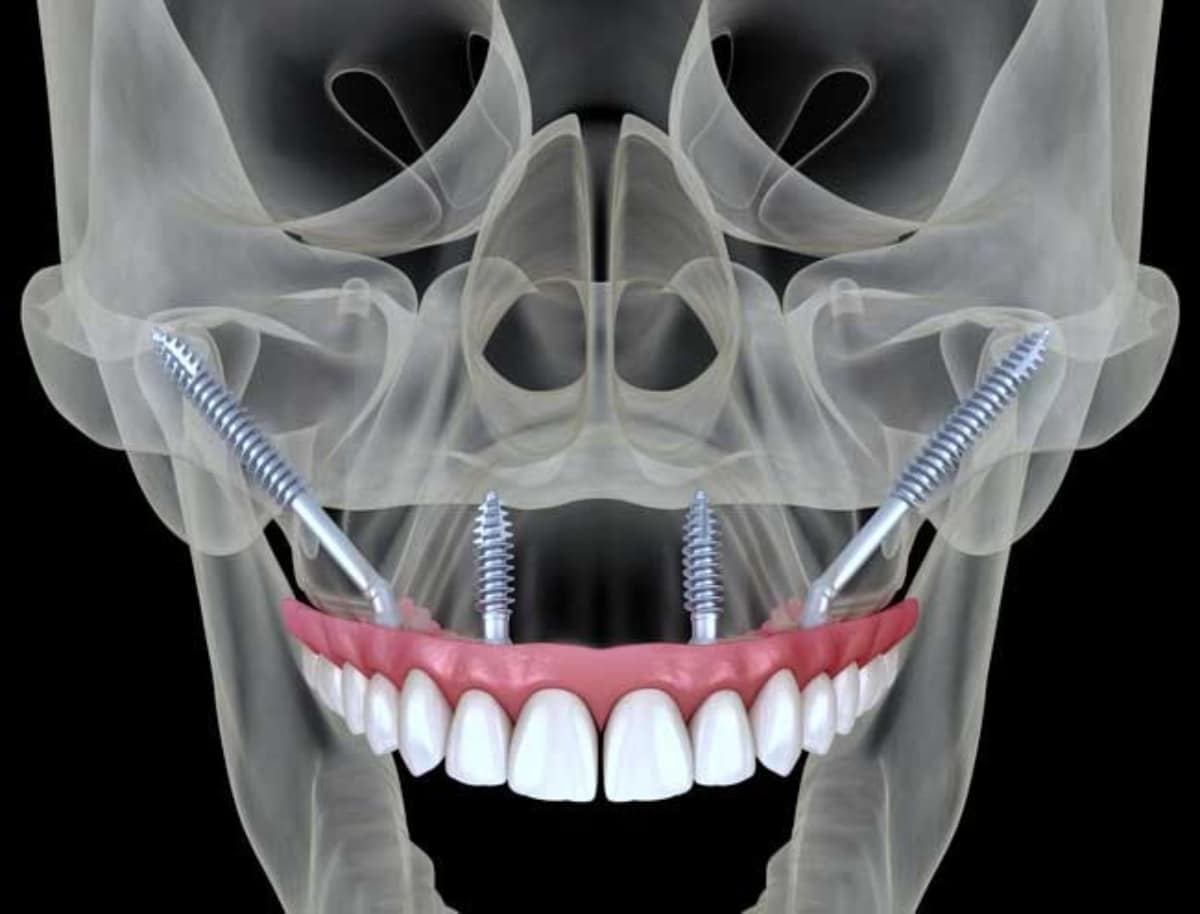

Can You Have Dental Implants with Severe Bone Loss? New Teeth Now

Solutions for Patients with Severe Bone Loss Who Want Dental Implants Dental Implant With Bone Loss Dental implants may help prevent bone loss that occurs after you lose a tooth. Web too much bone loss. Web prevents bone loss. Web dental implants are a good solution for people who are replacing teeth damaged by severe decay or trauma. One of the disadvantages of dental implants is that you need to have a strong jawbone to get.. Dental Implant With Bone Loss.

From drromanmelnyk.com